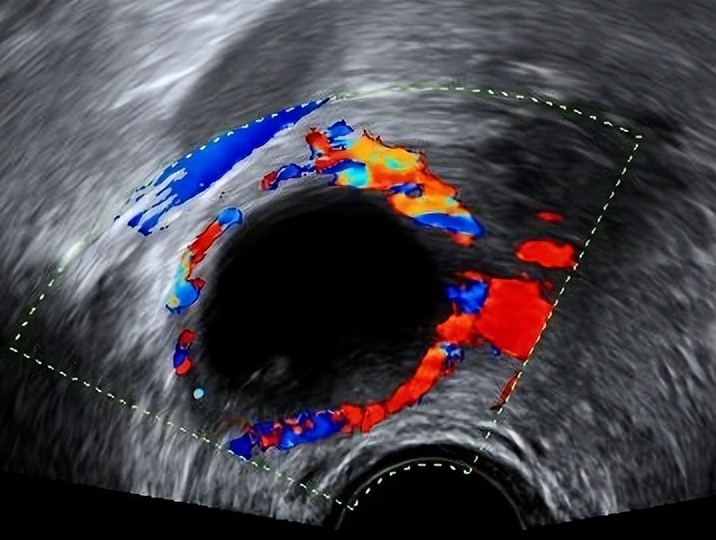

M5 |

有明显血流信号 |

B5 |

无血流信号 |